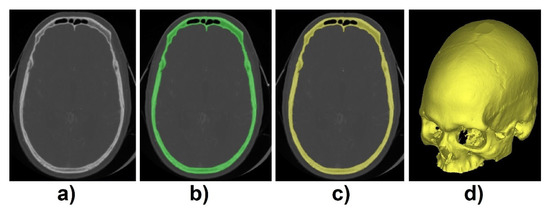

The dataset used to validate the proposed method was acquired from the qure.ai CQ500 dataset [9]. From this dataset, 195 images with 512 × 512 and varied depths were selected for training, validation, and test purposes. To create the ground truth labels, CT images were imported into Mimics Medical Imaging Software (Materialise, Leuven, Belgium). First, individual thresholding with manual corrections was applied for each of the 3D volumetric CT images. Then, region growing was applied to create the 3D model mesh. This process allowed for the creation of the standard tessellation language (STL) file format which was converted into a matrix using voxelization method [10] so we can easily process the file in MATLAB R2019b software (Mathworks, USA) (Figure 2).

Figure 2.

(a) Computed tomography (CT) scan, (b) thresholding applied, (c) region growing, and (d) 3D mesh model.